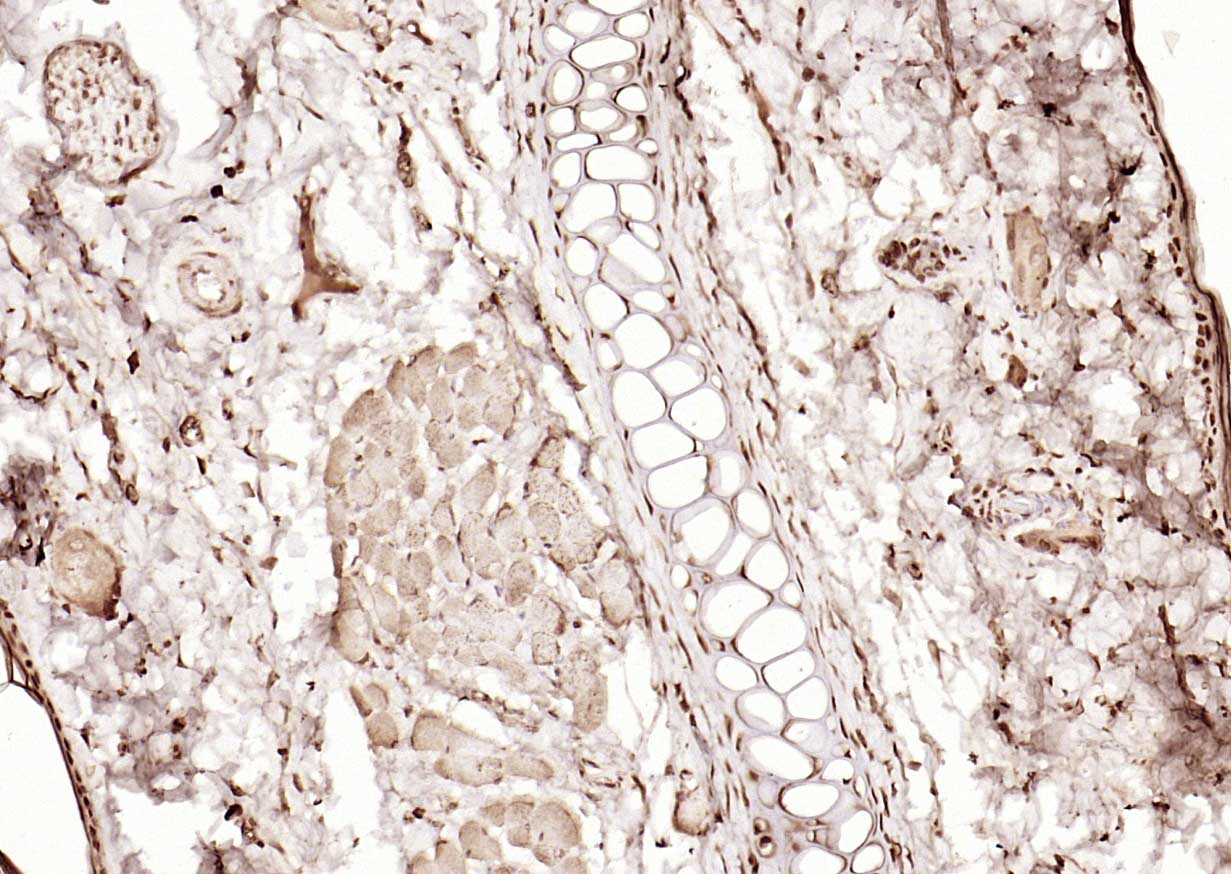

Paraformaldehyde-fixed, paraffin embedded (human gastric carcinoma); Antigen retrieval by boiling in sodium citrate buffer (pH6.0) for 15min; Block endogenous peroxidase by 3% hydrogen peroxide for 20 minutes; Blocking buffer (normal goat serum) at 37°C for 30min; Antibody incubation with (PPM1D) Polyclonal Antibody, Unconjugated (bs-22939R) at 1:200 overnight at 4°C, followed by operating according to SP Kit(Rabbit) (sp-0023) instructionsand DAB staining.

Paraformaldehyde-fixed, paraffin embedded (Human kidney); Antigen retrieval by boiling in sodium citrate buffer (pH6.0) for 15min; Block endogenous peroxidase by 3% hydrogen peroxide for 20 minutes; Blocking buffer (normal goat serum) at 37°C for 30min; Antibody incubation with (PPM1D) Polyclonal Antibody, Unconjugated (bs-22939R) at 1:200 overnight at 4°C, followed by operating according to SP Kit(Rabbit) (sp-0023) instructionsand DAB staining.

Paraformaldehyde-fixed, paraffin embedded (human laryngeal carcinoma); Antigen retrieval by boiling in sodium citrate buffer (pH6.0) for 15min; Block endogenous peroxidase by 3% hydrogen peroxide for 20 minutes; Blocking buffer (normal goat serum) at 37°C for 30min; Antibody incubation with (PPM1D) Polyclonal Antibody, Unconjugated (bs-22939R) at 1:200 overnight at 4°C, followed by operating according to SP Kit(Rabbit) (sp-0023) instructionsand DAB staining.

Paraformaldehyde-fixed, paraffin embedded (rat skin); Antigen retrieval by boiling in sodium citrate buffer (pH6.0) for 15min; Block endogenous peroxidase by 3% hydrogen peroxide for 20 minutes; Blocking buffer (normal goat serum) at 37°C for 30min; Antibody incubation with (PPM1D) Polyclonal Antibody, Unconjugated (bs-22939R) at 1:200 overnight at 4°C, followed by operating according to SP Kit(Rabbit) (sp-0023) instructionsand DAB staining.

Paraformaldehyde-fixed, paraffin embedded (mouse liver); Antigen retrieval by boiling in sodium citrate buffer (pH6.0) for 15min; Block endogenous peroxidase by 3% hydrogen peroxide for 20 minutes; Blocking buffer (normal goat serum) at 37°C for 30min; Antibody incubation with (PPM1D) Polyclonal Antibody, Unconjugated (bs-22939R) at 1:200 overnight at 4°C, followed by operating according to SP Kit(Rabbit) (sp-0023) instructionsand DAB staining.

Paraformaldehyde-fixed, paraffin embedded (human endometrial carcinoma); Antigen retrieval by boiling in sodium citrate buffer (pH6.0) for 15min; Block endogenous peroxidase by 3% hydrogen peroxide for 20 minutes; Blocking buffer (normal goat serum) at 37°C for 30min; Antibody incubation with (PPM1D) Polyclonal Antibody, Unconjugated (bs-22939R) at 1:200 overnight at 4°C, followed by operating according to SP Kit(Rabbit) (sp-0023) instructionsand DAB staining.

Paraformaldehyde-fixed, paraffin embedded (human rectal carcinoma); Antigen retrieval by boiling in sodium citrate buffer (pH6.0) for 15min; Block endogenous peroxidase by 3% hydrogen peroxide for 20 minutes; Blocking buffer (normal goat serum) at 37°C for 30min; Antibody incubation with (PPM1D) Polyclonal Antibody, Unconjugated (bs-22939R) at 1:200 overnight at 4°C, followed by operating according to SP Kit(Rabbit) (sp-0023) instructionsand DAB staining.

Paraformaldehyde-fixed, paraffin embedded (rat liver); Antigen retrieval by boiling in sodium citrate buffer (pH6.0) for 15min; Block endogenous peroxidase by 3% hydrogen peroxide for 20 minutes; Blocking buffer (normal goat serum) at 37°C for 30min; Antibody incubation with (PPM1D) Polyclonal Antibody, Unconjugated (bs-22939R) at 1:200 overnight at 4°C, followed by operating according to SP Kit(Rabbit) (sp-0023) instructionsand DAB staining.

Paraformaldehyde-fixed, paraffin embedded (rat testis); Antigen retrieval by boiling in sodium citrate buffer (pH6.0) for 15min; Block endogenous peroxidase by 3% hydrogen peroxide for 20 minutes; Blocking buffer (normal goat serum) at 37°C for 30min; Antibody incubation with (PPM1D) Polyclonal Antibody, Unconjugated (bs-22939R) at 1:200 overnight at 4°C, followed by operating according to SP Kit(Rabbit) (sp-0023) instructionsand DAB staining.

Paraformaldehyde-fixed, paraffin embedded (rat kidney); Antigen retrieval by boiling in sodium citrate buffer (pH6.0) for 15min; Block endogenous peroxidase by 3% hydrogen peroxide for 20 minutes; Blocking buffer (normal goat serum) at 37°C for 30min; Antibody incubation with (PPM1D) Polyclonal Antibody, Unconjugated (bs-22939R) at 1:200 overnight at 4°C, followed by operating according to SP Kit(Rabbit) (sp-0023) instructionsand DAB staining.

Paraformaldehyde-fixed, paraffin embedded (mouse kidney); Antigen retrieval by boiling in sodium citrate buffer (pH6.0) for 15min; Block endogenous peroxidase by 3% hydrogen peroxide for 20 minutes; Blocking buffer (normal goat serum) at 37°C for 30min; Antibody incubation with (PPM1D) Polyclonal Antibody, Unconjugated (bs-22939R) at 1:200 overnight at 4°C, followed by operating according to SP Kit(Rabbit) (sp-0023) instructionsand DAB staining.

Paraformaldehyde-fixed, paraffin embedded (mouse brain); Antigen retrieval by boiling in sodium citrate buffer (pH6.0) for 15min; Block endogenous peroxidase by 3% hydrogen peroxide for 20 minutes; Blocking buffer (normal goat serum) at 37°C for 30min; Antibody incubation with (PPM1D) Polyclonal Antibody, Unconjugated (bs-22939R) at 1:200 overnight at 4°C, followed by operating according to SP Kit(Rabbit) (sp-0023) instructionsand DAB staining.